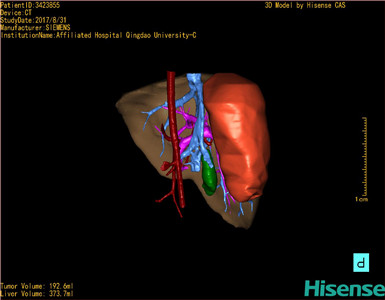

将0.625mm双源薄层CT资料的静脉期和动脉期Dicom格式文件导入海信CAS系统。

通过调节窗宽窗位调整CT序号,对肝实质,胆囊,下腔静脉,肿瘤,肝动脉、门静脉及肝静脉等进行三维重建;系统自动计算肝脏体积。

模拟手术操作,自动计算切除肿瘤体积。肝脏体积为373.7ml,肿瘤体积是192.6ml,是肝脏体积的0.5倍,通过比对2-3岁正常肝脏体积为475.97±99.7ml,通过术前模拟手术,精准判断切除后剩余肝脏体积能耐受,避免肝衰竭发生。

术前三维重建:

重建图片